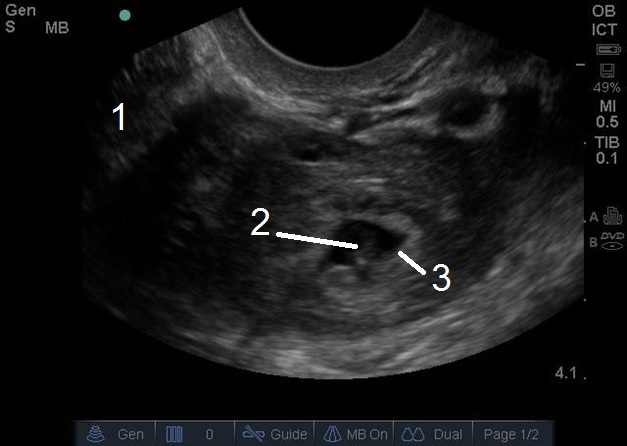

Bild 1: Transvaginaler (TV) Ultraschall des Beckens, ektopische Schwangerschaft, Adnexe

1. Uterus

2. Ektopisch

3. Gestationssack